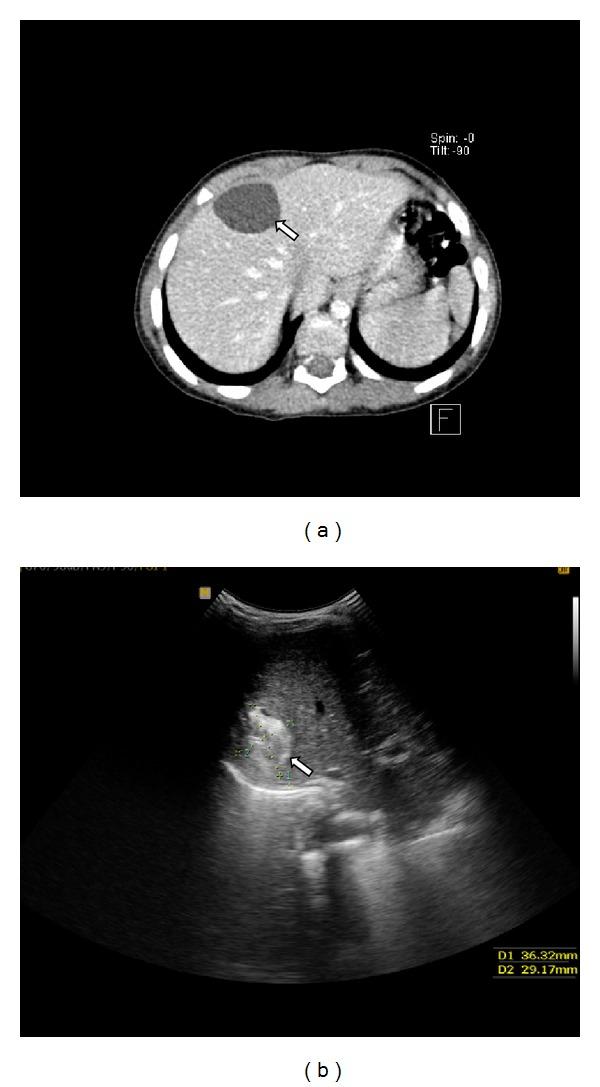

Ciliated hepatic foregut cyst (CHFC) is a rare lesion which originates from detached hepatic diverticulum or from detachment and migration of buds from the esophageal and bronchial regions of the foregut which subsequently get entrapped by the liver during the early embryonic development of the foregut. CHFCs are mostly seen in adults and are rarely reported in children, with only about 10 cases reported in this age group. Hereby, we present two cases of CHFC in two 3.5-year-old boys; one of them had cystic lesion at medial segment of left lobe of liver (common site), and in the other one it was located at right lobe of liver (less common site). Histologically, both cysts had four layers composed of inner ciliated, pseudostratified, columnar epithelium; subepithelial connective tissue; smooth muscle layer; and an outer fibrous layer.

纤毛肝前肠囊肿(CHFC)是一种罕见的病变,它起源于分离的肝憩室,或源于前肠食管和支气管区域芽的分离与迁移,这些芽在胚胎早期前肠发育过程中随后被肝脏包绕。CHFC多见于成年人,儿童中很少报道,该年龄组仅有约10例报告。在此,我们报告两例3.5岁男孩的CHFC;其中一例在肝左叶内侧段有囊性病变(常见部位),另一例位于肝右叶(较少见部位)。组织学上,两个囊肿均有四层结构,由内向外依次为纤毛假复层柱状上皮、上皮下结缔组织、平滑肌层和外层纤维层。